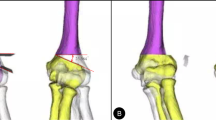

To evaluate the 3D humerus deformity using a surface-based registration technique [25, 26], the affected humerus was compared with a mirror image of the contralateral normal humerus (Fig. 2). The 3D varus, extension, and internal rotation deformities were quantified by superimposing the proximal parts of the affected humerus onto those of the mirror image of the normal humerus and calculating the rotation angles of the distal parts, according to previous studies that used the Euler angle method [3, 10]. In this study, we calculated the absolute values of the deformity angles in the coronal, sagittal, and axial directions relative to those in the contralateral normal humerus to investigate the remodelling. In our cohort, 43 (50%), 19 (22%), 14 (16%), and ten (12%) participants had coronal–axial, triplane, coronal, and coronal–sagittal direction deformities, respectively; a deformity > 5° was considered significant [27, 28].

Three-dimensional (3D) deformity of the distal humerus The proximal site of the affected humerus is superimposed on a mirror image of the contralateral normal humerus. Next, the 3D deformity of the distal site was quantified in three directions: varus (coronal direction), extension (sagittal direction), and rotation (axial direction)